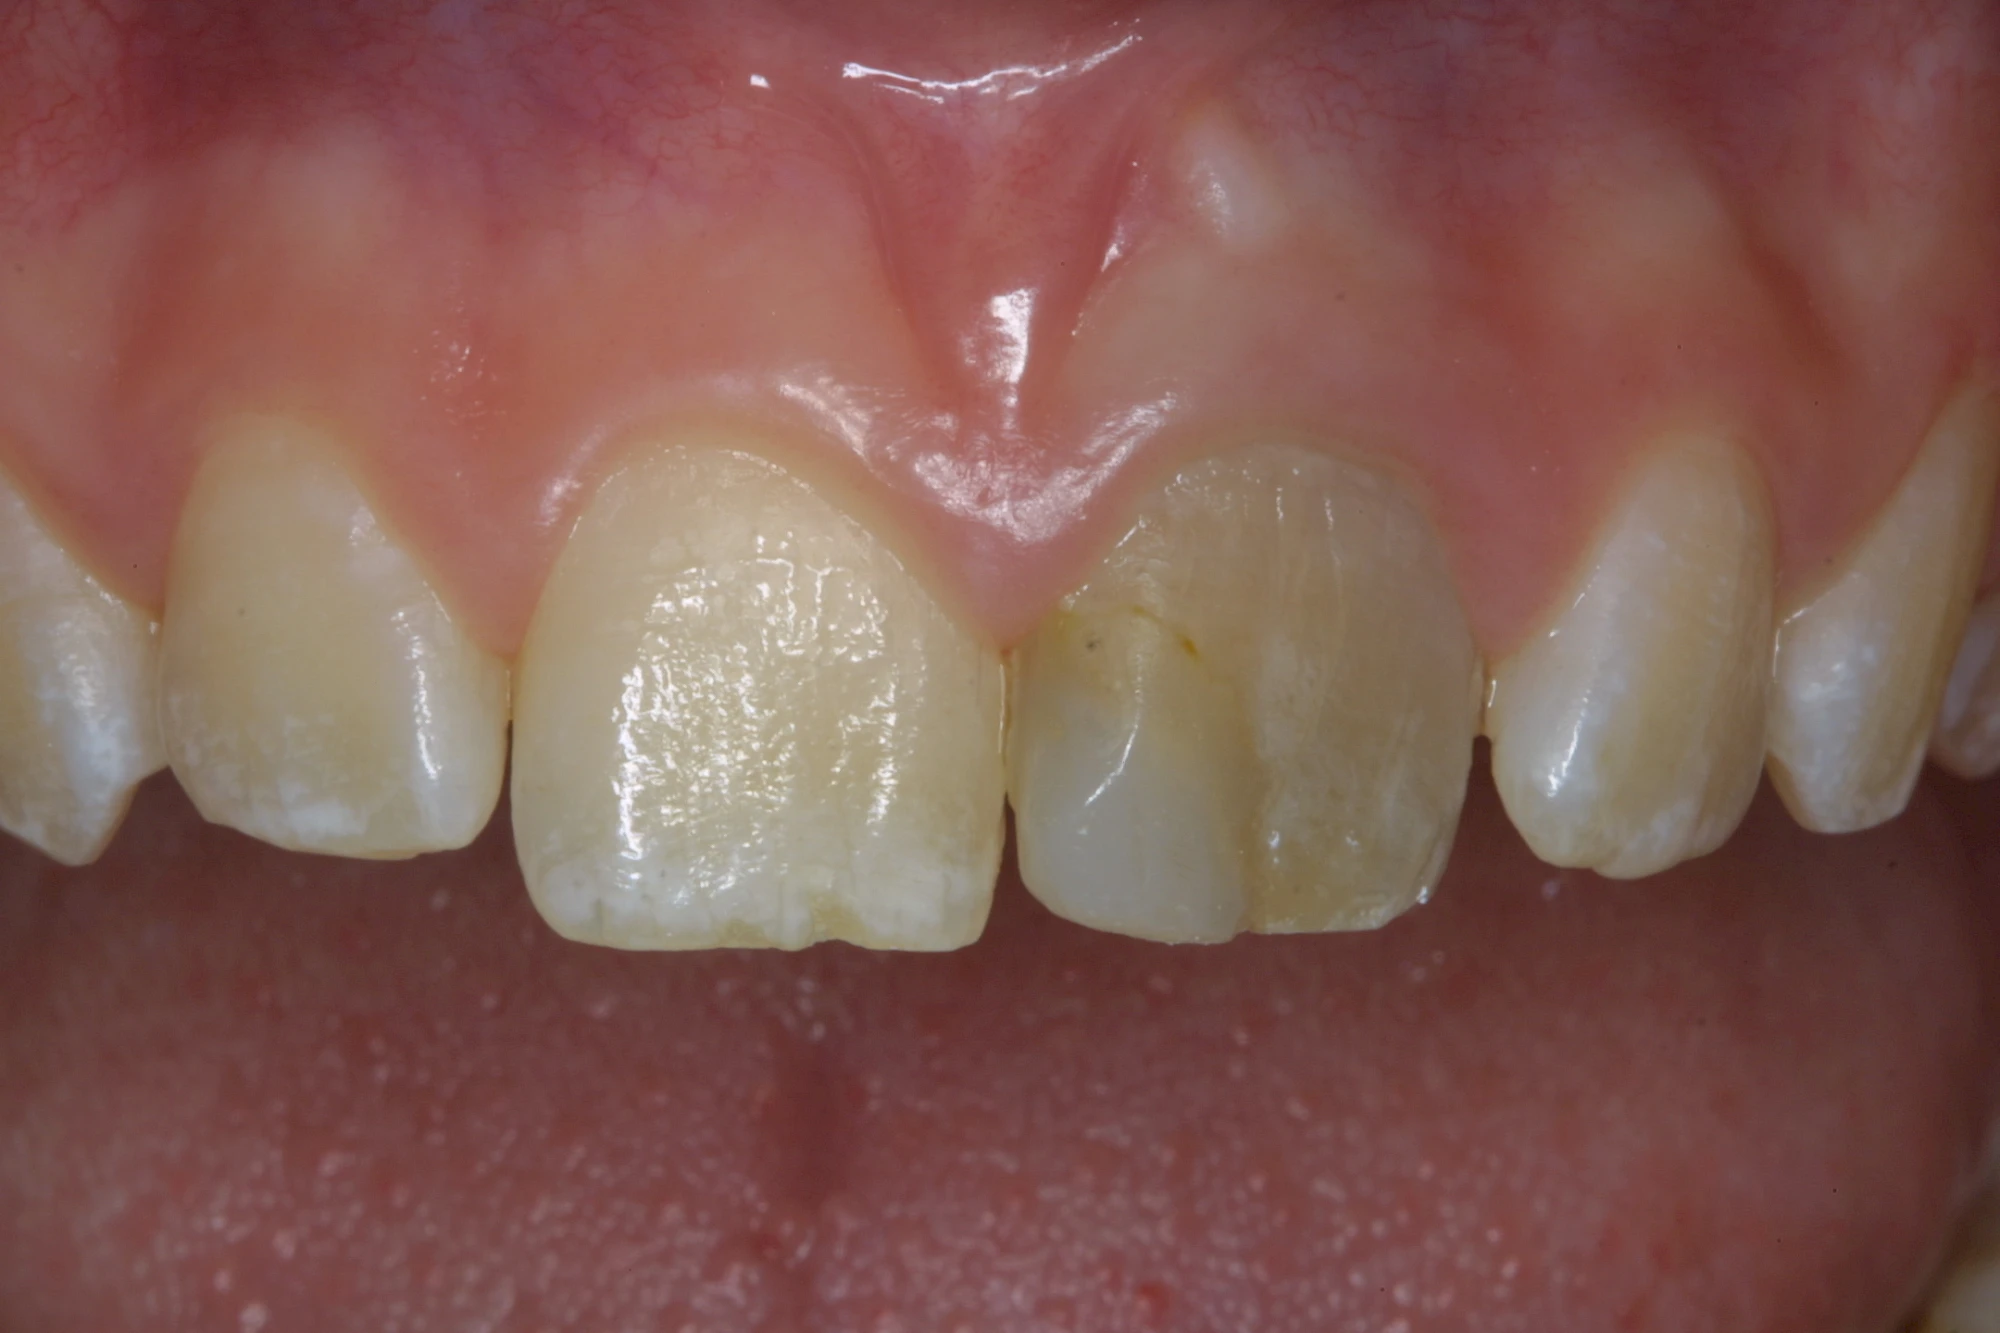

Von innen (endogen)

- Durch Blutabbauprodukte, weil der Zahnnerv abgestorben (einzelner Zahn, dunkel-flächig)

- Durch übermäßige Fluorideinlagerung in der Zahnreifung (mehrere Zähne, weißlich-fleckig)

Dunkle bzw. Rötliche Verfärbung

Ist ein einzelner Zahn deutlich dunkler als die Nachbarzähne kann das ein Zeichen sein, dass der Nerv abgestorben ist. Unter Umständen wurde bereits eine Wurzelkanalbehandlung vom Zahnarzt durchgeführt. Eine Abklärung durch den Zahnarzt ist in jedem Fall sinnvoll.